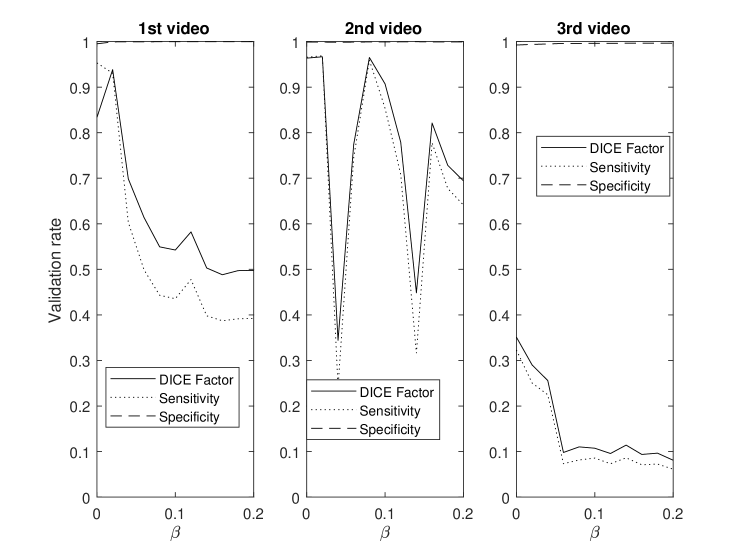

This section demonstrates the robustness of the algorithm for each parameter along with the relative importance of each parameter on the overall performance. This enables the identification and potential removal of weak features from the energy function in order to improve computational efficiency. For this study, the average DICE factor, sensitivity, and specificity of three different clips versus the initial parameters , , , , and are shown in Figs. 5-10. In the all of these figures, one can easily see that the specificity is always very close to one indicating a relatively small rate of .

The parameter demonstrates optimal performance near zero as per Fig. 6. This strongly suggests that the continuity energy term is a weak feature and hence, can be removed from the energy function.